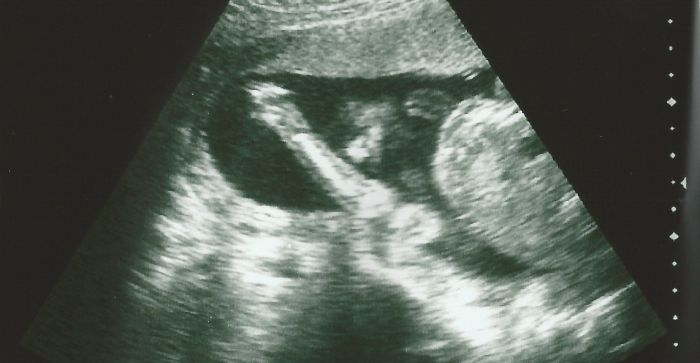

Laurinko, ty snímky jsou krásný, je na nich pěkně holčička vidět.

ted jsem si uvědomila,že jsem zapomněla přiložit fotečku naší malinké, jak nám krásně mává :) plus přiložím dnešní bazárkový ulovek, z kterého jsem paf :D samozřejmě,že růžový :DD